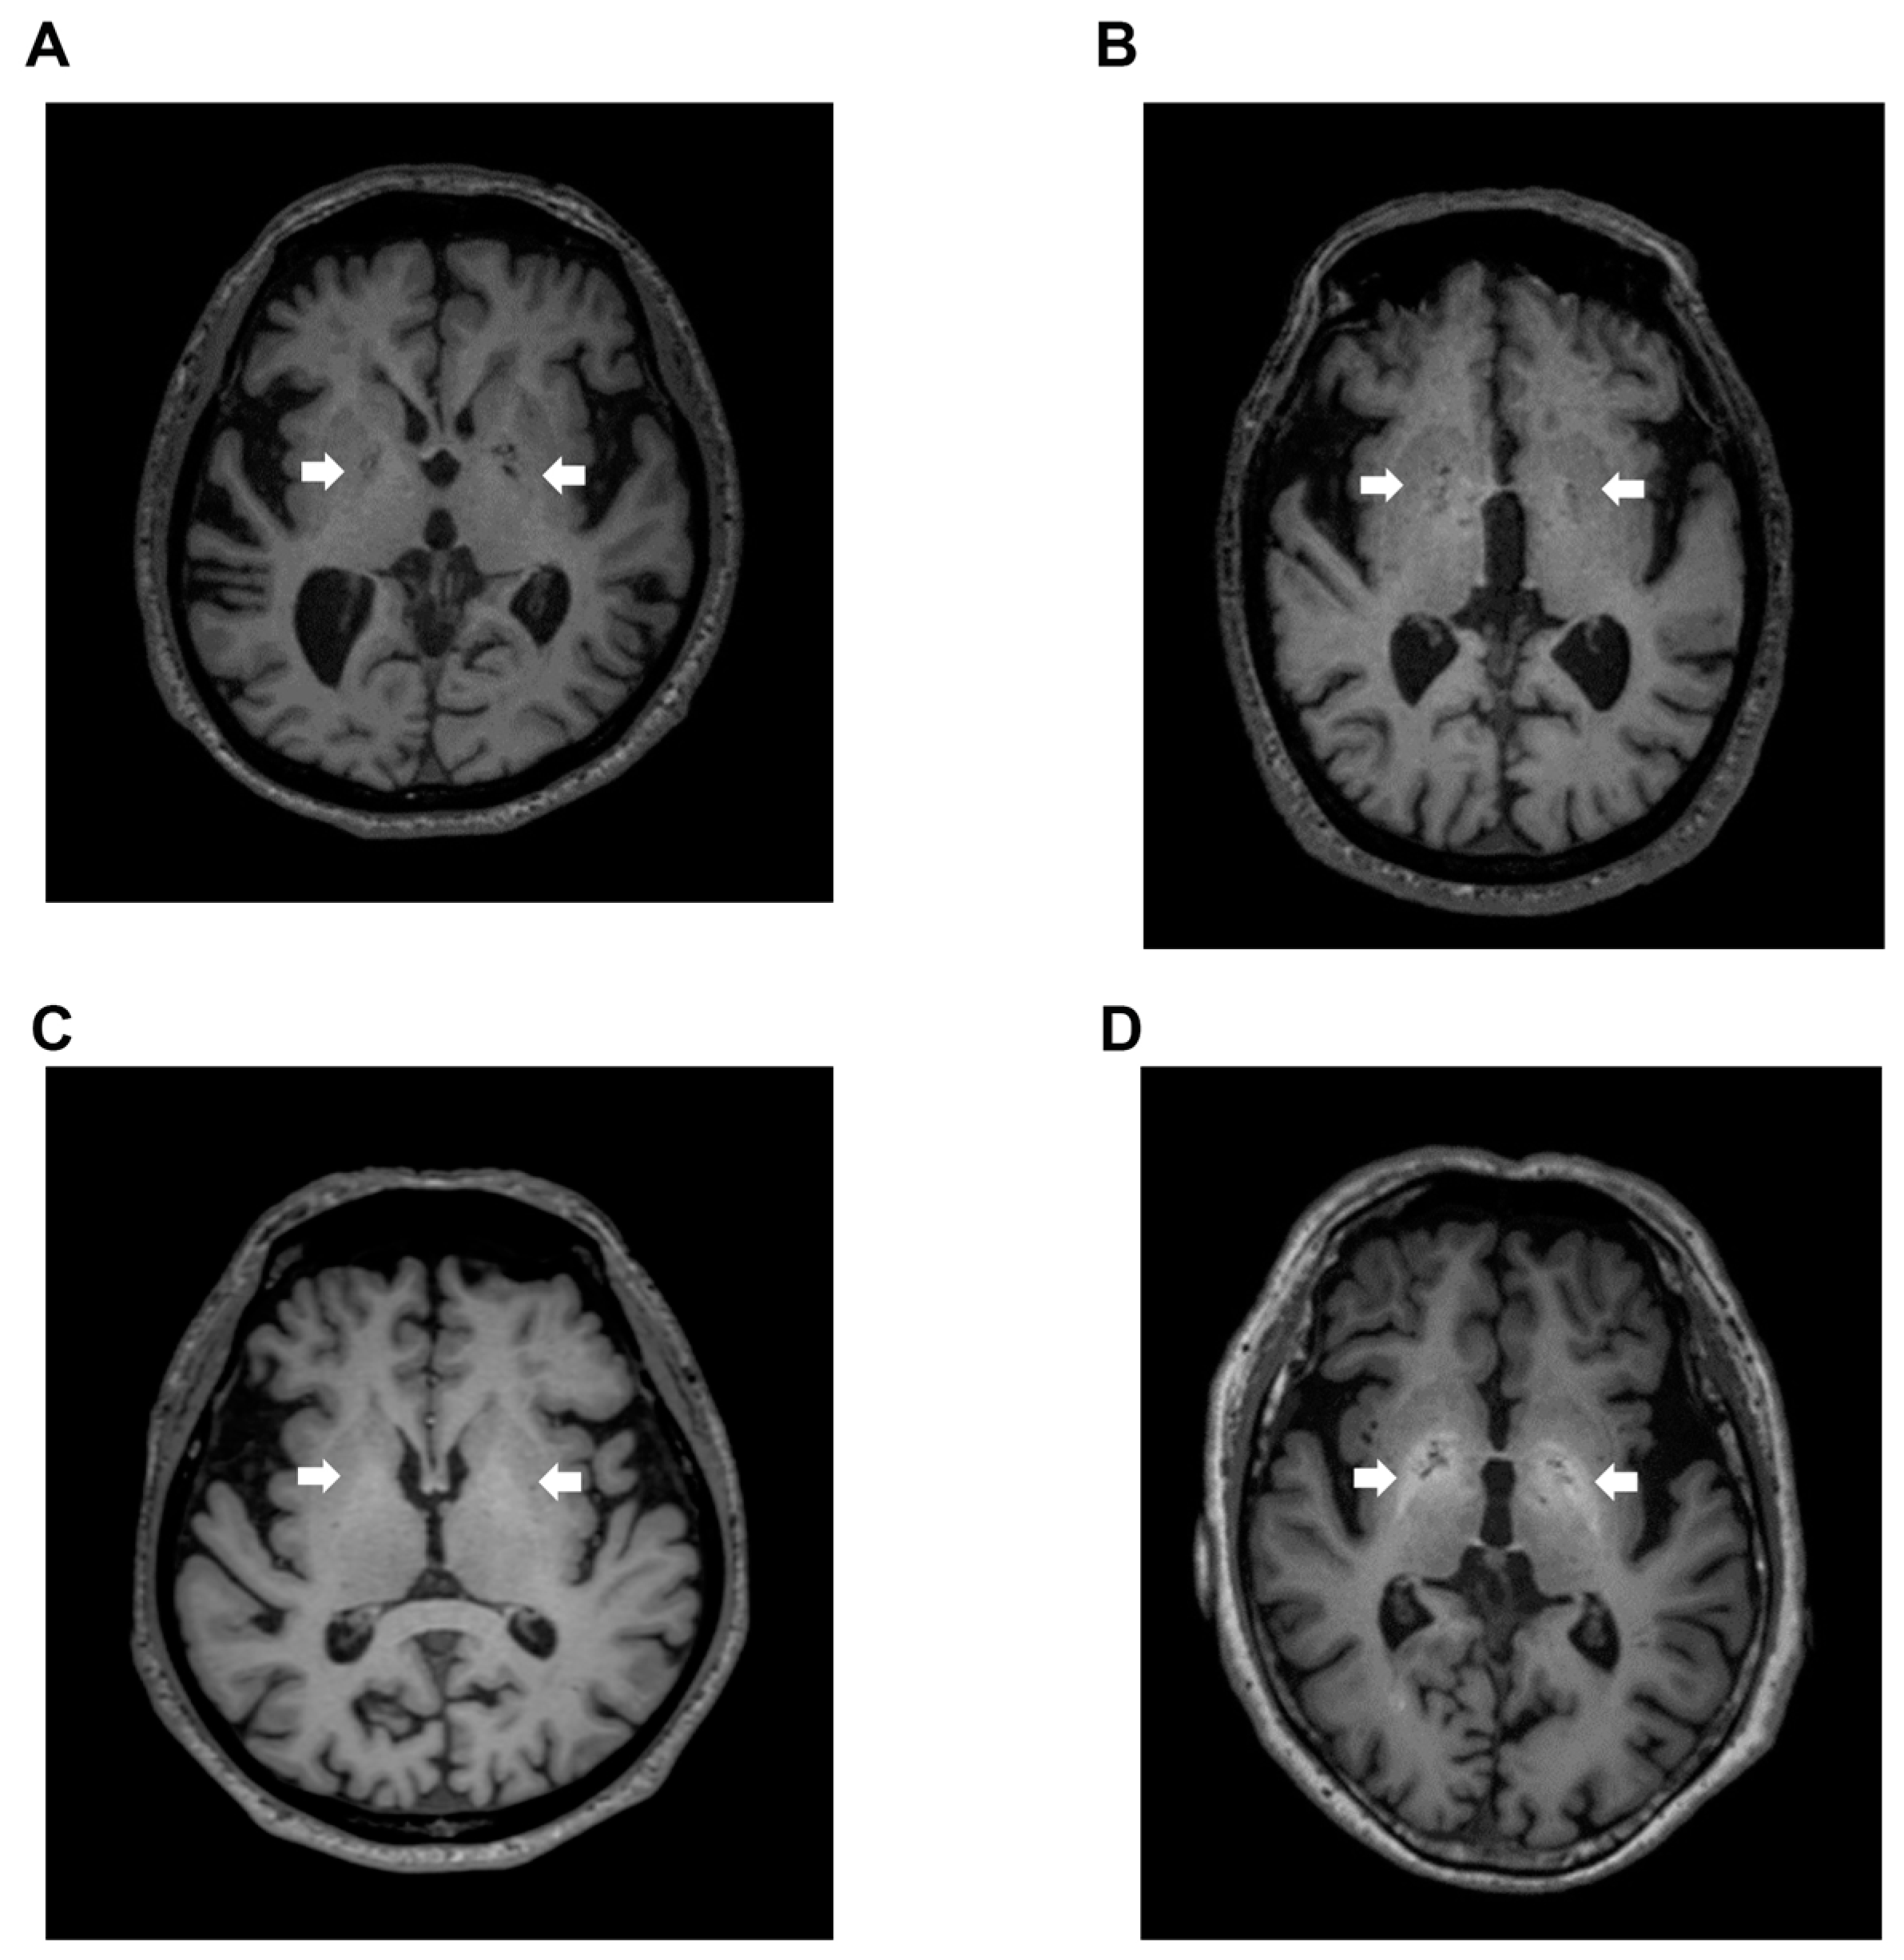

Signal intensity value of GP (arrow) in transverse T1-weighted imaging was mildly increased (Figure 2B,C) or clearly increased (Figure 2D) on a case-by-case basis, when compared to healthy subject (Figure 2A). Indeed, the signal intensity of GP in LC patients with HE was dramatically increased compared to the values seen in LC patients without HE (p < 0.05), healthy subjects (p < 0.05), and dementia patients (p < 0.001). Contrarily, the signal intensity of GP observed in dementia patients was markedly decreased when compared to those seen in LC patients with HE (p < 0.001), LC patients without HE (p < 0.001), and healthy subjects (p < 0.05) (Figure 3).

Figure 2. T1-weighted images. (A) Transverse T1-weighted imaging from a 74-year-old healthy subject. Signal intensity value of GP (arrow) was 0.952, which is below the cut-off value of 0.994; (B) Transverse T1-weighted imaging from a 79-year-old LC patient. Signal intensity value of GP (arrow) was 0.992, also below the cut-off value of 0.994; (C) Transverse T1-weighted imaging from a 63-year-old LC patient. Signal intensity value of GP (arrow) was 1.006, which exceeded the cut-off value of 0.994; (D) Transverse T1-weighted imaging from a 68-year-old HE patient. Signal intensity value of GP (arrow) was 1.024, also exceeding the cut-off value of 0.994. GP, globus pallidus; LC, liver cirrhosis; HE, hepatic encephalopathy.